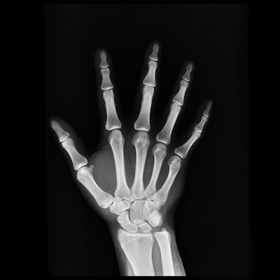

After testing our proposed method on several synthetic images, we now consider applying it on real medical images. Here, we consider a hand X-ray image as the source image (Fig. 7(a)) and a deformed hand X-ray image as the target image (Fig. 7(b)). Fig. 7(c) shows the original absolute intensity difference between the two images. It can be observed that different fingers are displaced in a nonuniform manner (for example, the displacement of the index finger is much larger than that of the little finger), while the wrist remains almost the same. Therefore, a simple rigid transformation is insufficient for yielding a good registration. As shown in Fig. 7(d), our proposed method successfully deforms the source image to match the target image, and the final intensity difference is significantly smaller (see Fig. 7(e)). From the deformed underlying grid in Fig. 7(f), it can be observed that the mapping is smooth and bijective. For comparison, both LDDMM [5] and DDemons [47] fail to register the fingers and are non-bijective (see Fig. 7(g), Fig. 7(h), and Fig. 7(i)).

We then consider another example of registering two hand X-ray images with larger deformations (see Fig. 8(a) for the source image, Fig. 8(b) for the target image, and Fig. 8(c) for their absolute intensity difference). The warped image produced by our proposed method (Fig. 8(d)) again closely resembles the target image with the intensity difference significantly reduced (see Fig. 8(e)). Fig. 8(f) shows that the mapping is smooth and bijective. For comparison, note that LDDMM [5] fails to match the fingers (Fig. 8(g)). While DROP [18] is capable of registering the fingers (Fig. 8(h)), it distorts the boundary shape of the overall image (Fig. 8(i)).

Refer to caption

(a) Source image

(b) Target image

(c) Intensity difference

(d) Our registration result

(e) Final intensity difference

(f) Warped image with grid

(g) Result by LDDMM [5]

(h) Result by DROP [18]

(i) DROP deformed grid

Figure 8. The second hand X-ray example.